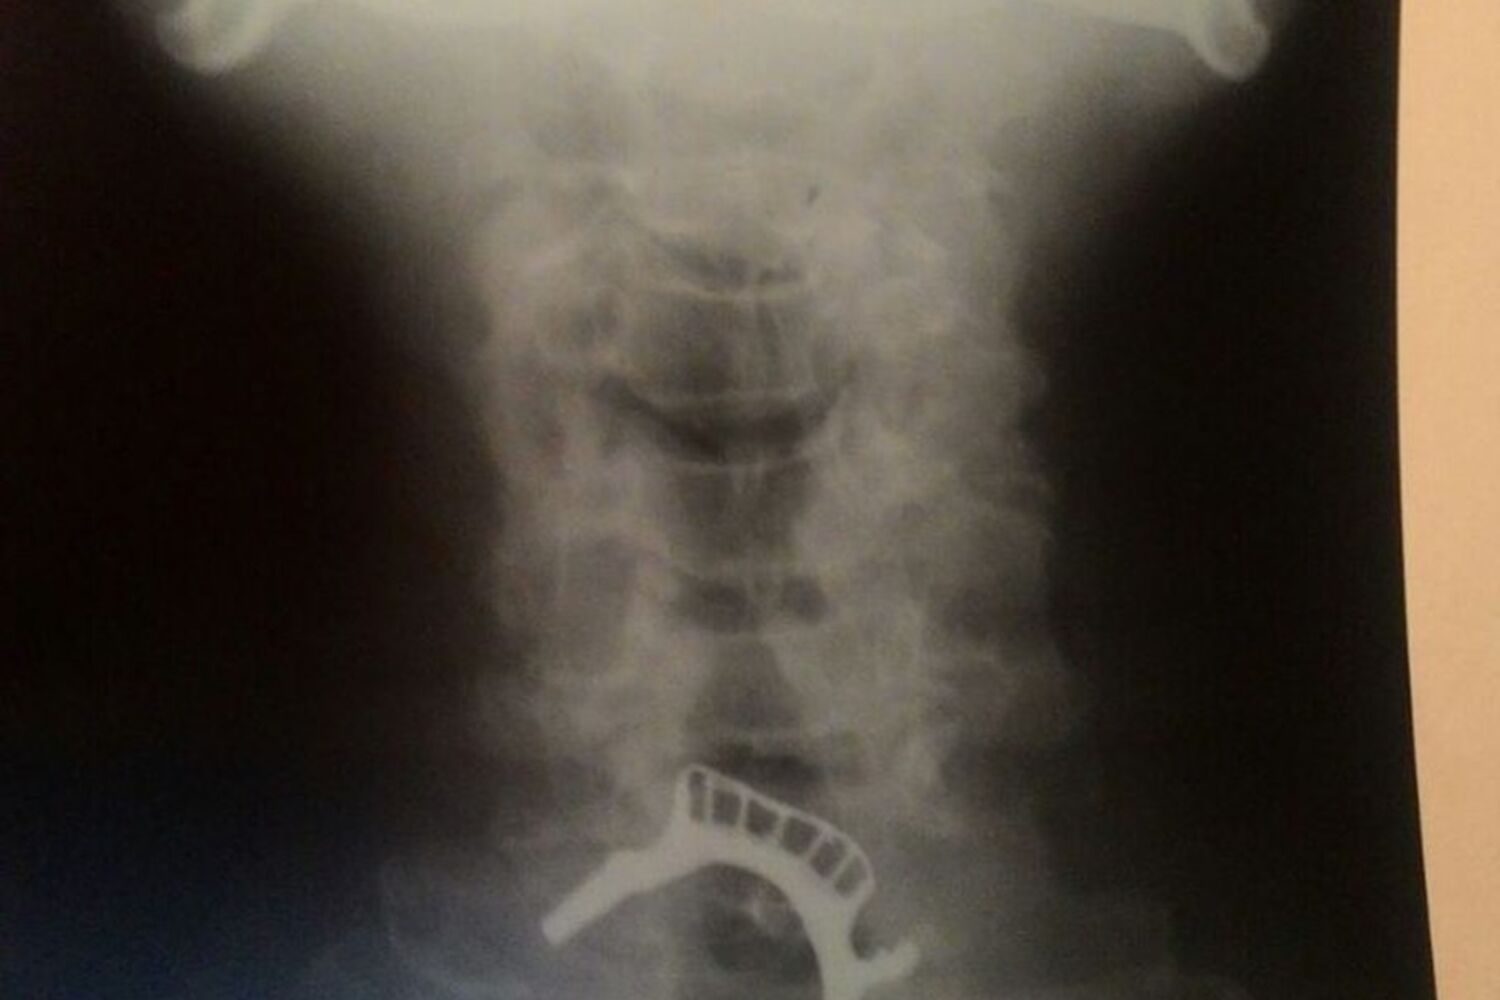

Segundo o site G1, que falou com a filha de Antonio, foi feito um raio-X para verificar que a dentadura estava presa. Foi dito à família que era preciso um aparelho de endoscopia para verificar a situação e de que forma seria possível retirar a prótese. No entanto o hospital não dispunha do aparelho há vários dias.

Com efeito, ao fim de 40 horas, a protése dentária  que o homem tinha alojada na garganta foi retirada em 20 minutos, tendo o brasileiro voltado para o hospital de Ferraz, de onde teve alta no final da tarde de quinta-feira.